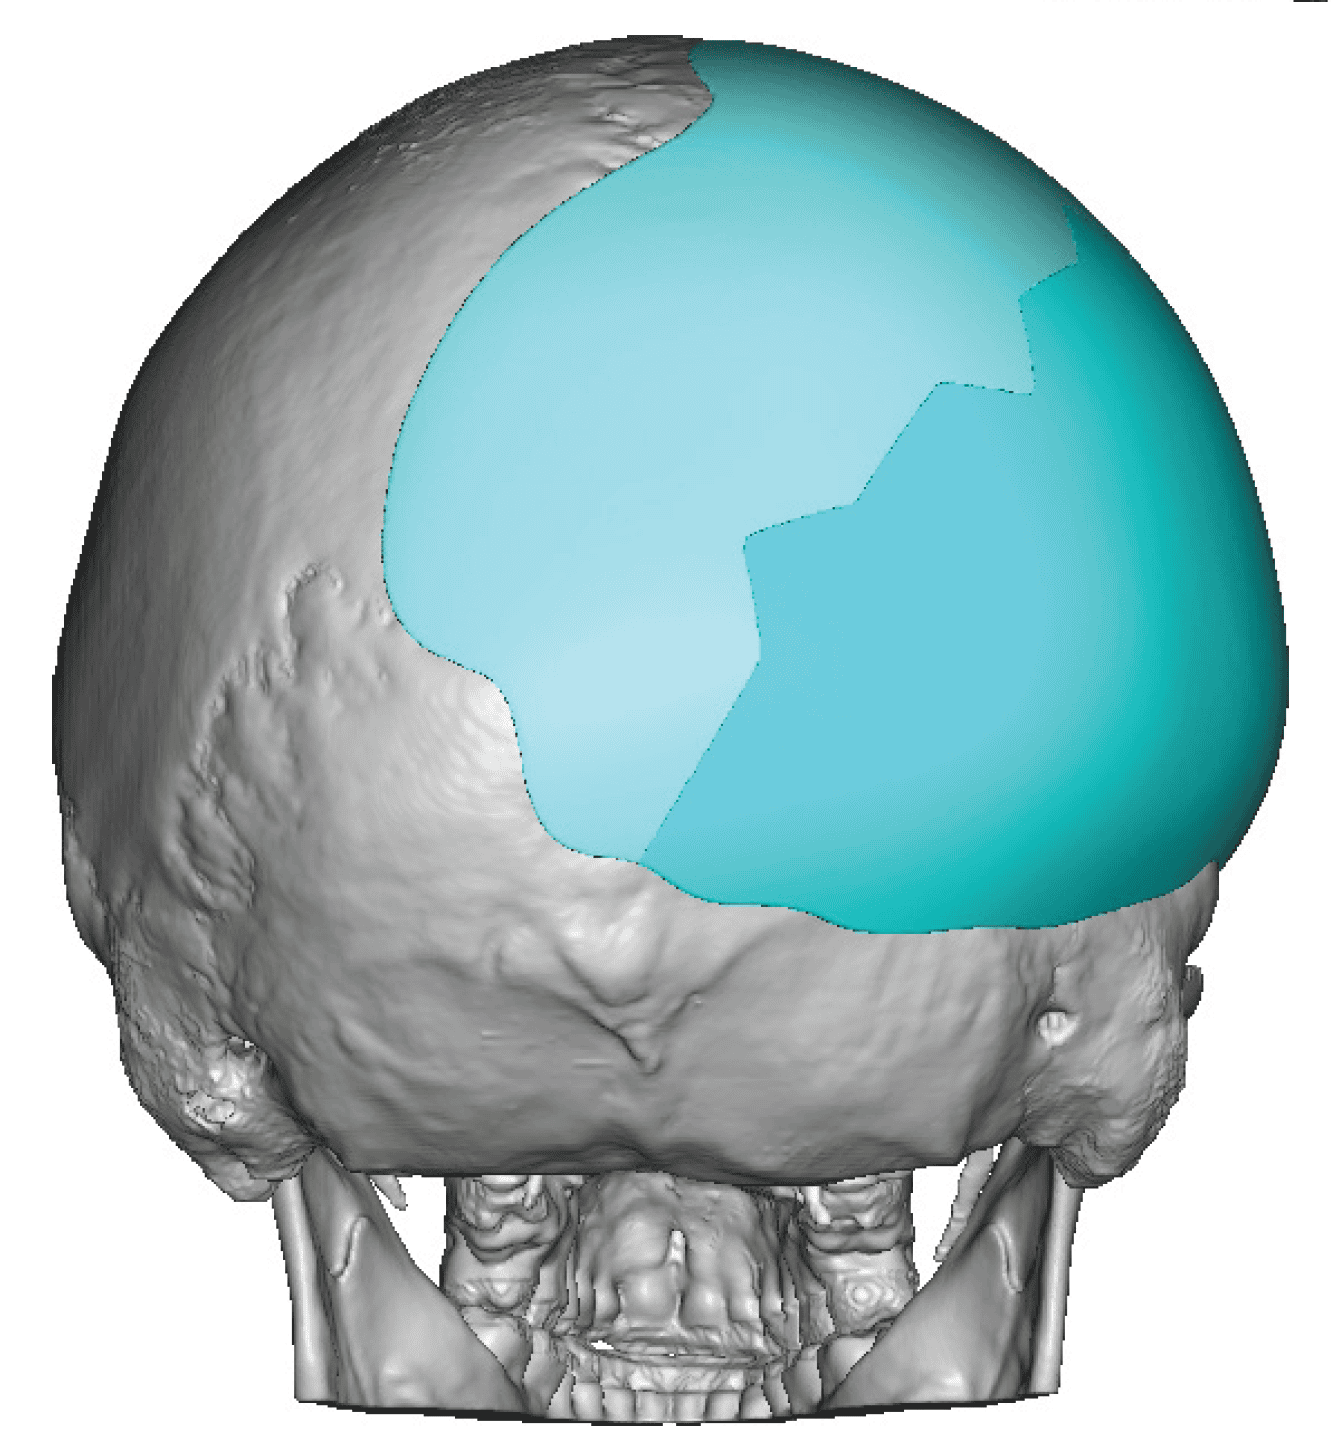

Severe narrowing skull deformity from prior sagittal craniosynostosis repair as an adult.

Complete replacement of entire skull by a custom implant with temporal fat injections.

Severe narrowing skull deformity from prior sagittal craniosynostosis repair as an adult.

Complete replacement of entire skull by a custom implant with temporal fat injections.